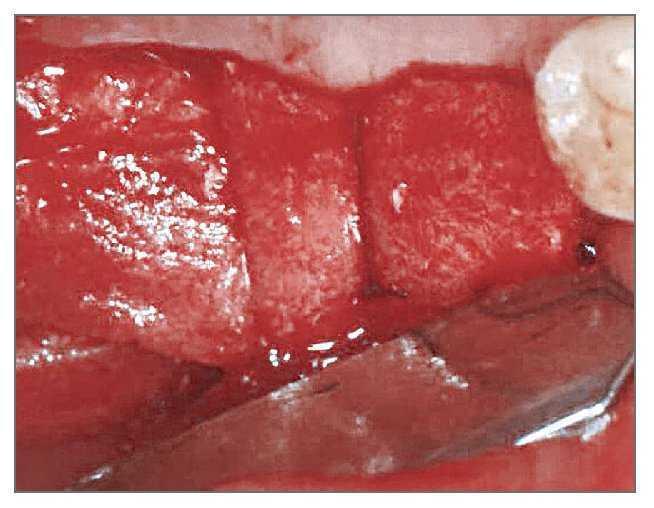

El paciente se enjuagó con colutorio de clorhexidina al 0,12% (Hexamedine, Bukwang) durante 2 min antes de la operación. Después de aplicar anestesia local con lidocaína al 2% y epinefrina 1:100.000, se levantó un colgajo de espesor total, poniendo de manifiesto el defecto óseo del alveolo vestibular. La dehiscencia vestibular era de 2,0 a 6,0 mm apicoronalmente. Se colocaron tres implantes de 3,8 x 12,0 mm (Implantium, Dentium) en el área molar de la mandíbula derecha con un torque de inserción de 40 Ncm (fig. 2). El defecto remanente y los vacios marginales se injertaron con hueso bovino deproteinizado (Bio-Oss, Geistlich Pharm) (fig. 3). Se empleó MDA para cubrir completamente el injerto óseo y asegurarlo bajo los colgajos vestibular y lingual (fig. 4). A continuación, se reposicionó el colgajo y se cerró la herida con suturas simples (Ethicon, Johnson & Johnson Medical).

Figura 3 (derecha). El área del defecto vestibular se rellenó con hueso bovino deproteinizado.